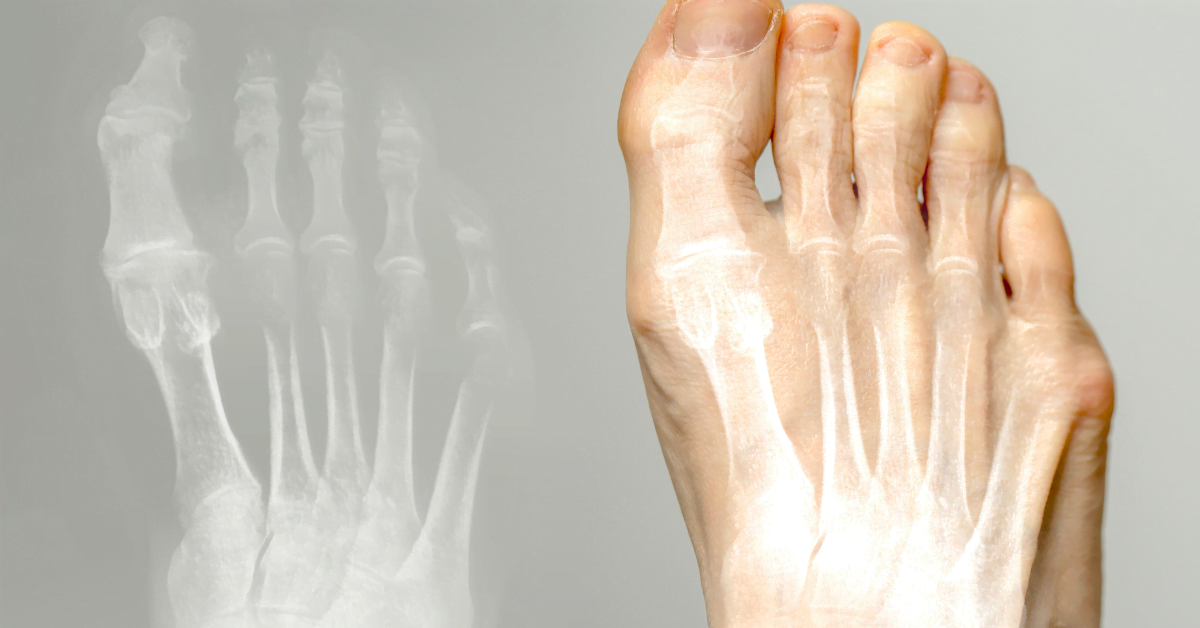

Hallux valgus (juanete) es una afección en la que el dedo gordo del pie se inclina hacia adentro y forma un bulto en la base. Puede causar dolor y molestias. Aquí lees causas, tratamiento y prevención.

El dedo gordo se dobla hacia los otros dedos, formando un bulto en el pie. Causas: zapatos estrechos, tacones altos, herencia, pies planos o artritis. El calzado inadecuado causa presión y fricción, lo que puede provocar bursitis.

Bulto en la base del dedo gordo, dolor al usar zapatos, enrojecimiento e hinchazón. Sensación de ardor, dificultad para caminar. A veces artrosis en el dedo gordo.

El hallux valgus es una desviación del dedo gordo del pie hacia adentro, con un bulto en la base. A menudo causado por zapatos estrechos, tacones altos o herencia. Puede causar dolor y bursitis.